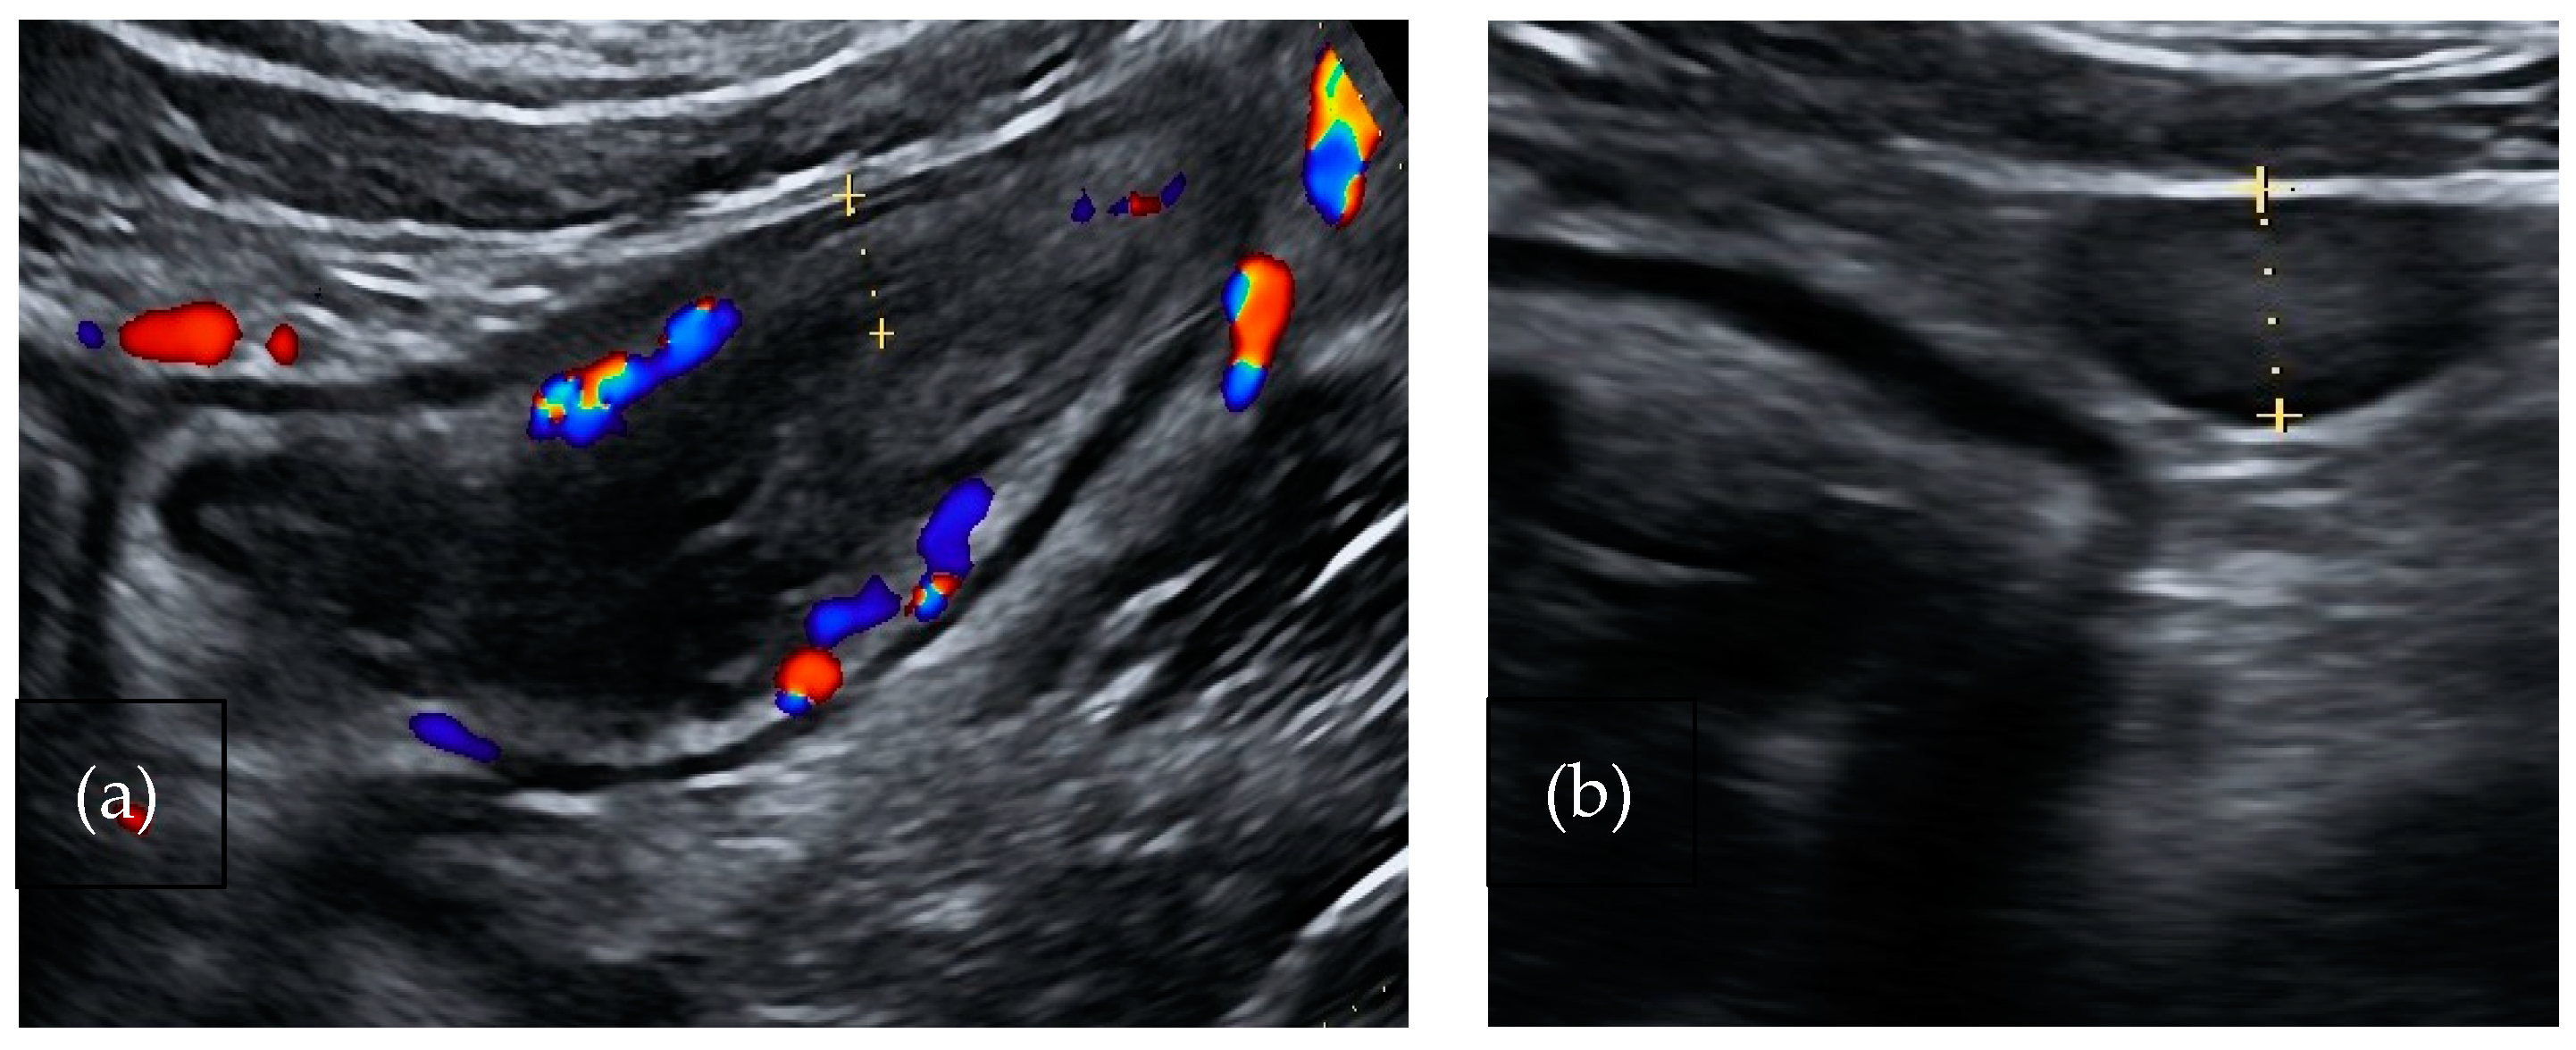

Salmonella and Campylobacter are Gram-negative bacteria responsible for self-limiting ileocecal infections. The typical involvement of terminal ileum and caecum determines acute right lower abdominal pain (Figure 1a,b). Diarrhea is absent or mild and stool cultures are not always requested; therefore, diagnosis is delayed. These symptoms are frequently considered as clinical signs of appendicitis and often lead to an unnecessary appendicectomy. US findings include marked hyperechoic thickening of the mucosa and submucosa of the terminal ileum and caecum with or without lymphadenopathy. Mesenteric fat and the appendix are not involved [31].

Figure 1.

A 37-year-old-man affected by Campylobacter infection. (a). Bowel ultrasound shows thickening of the right colon wall (5.8 mm) with active inflammation (color flow Doppler signals in both the bowel wall and surrounding mesenteric fat). (b). Presence of lymphadenopathy.